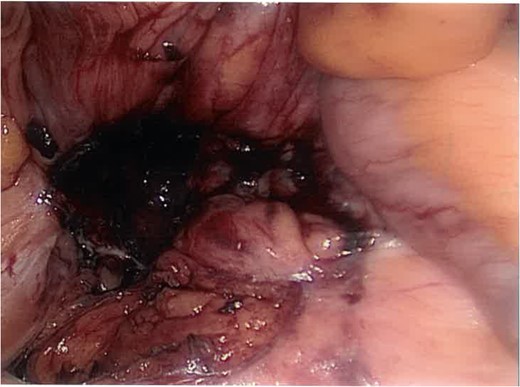

Intra-operatively multiple adhesions were lysed, and the caecum was found to be adherent to the posterior wall. It was freed up and inverted to reveal an inflammatory mass in the right para-colic gutter underlying the ascending colon. Dissection of the overlying inflamed tissue revealed a walled-off gallstone (Fig. 2).

Laparoscopic view of the dropped stone in the right para-colic gutter (caecum inverted top right).